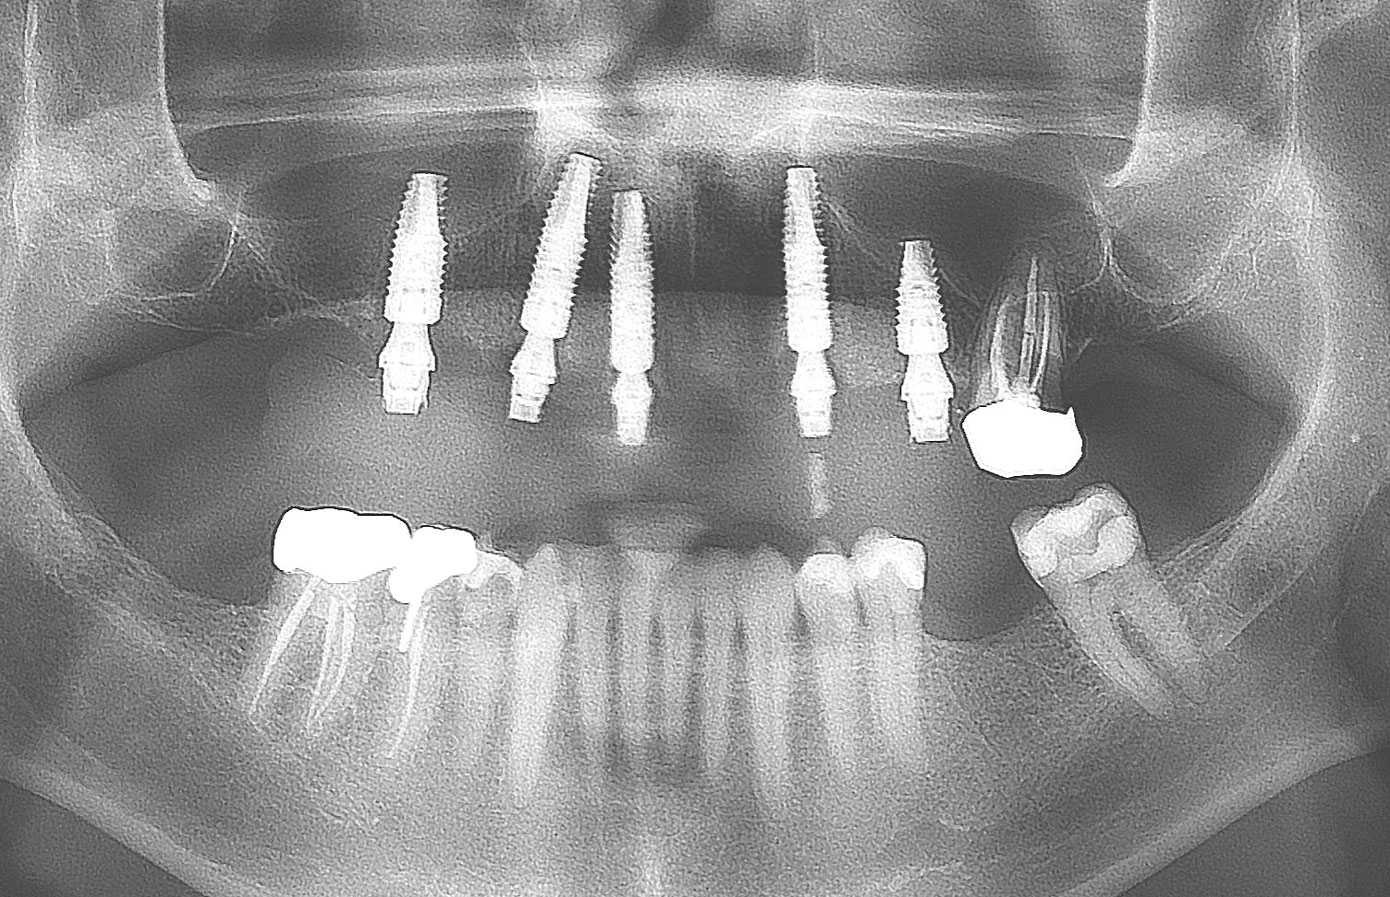

Fig 11. Initial panoramic radiograph.

Figure 11

At the initial visit, a panoramic x-ray (Figure 11) and periapical x-rays were taken. The patient was photographed to capture her full face and shoulders, and a digital scan of the maxillary dentition was obtained. This file was electronically sent to the implant company to complete the VSD.